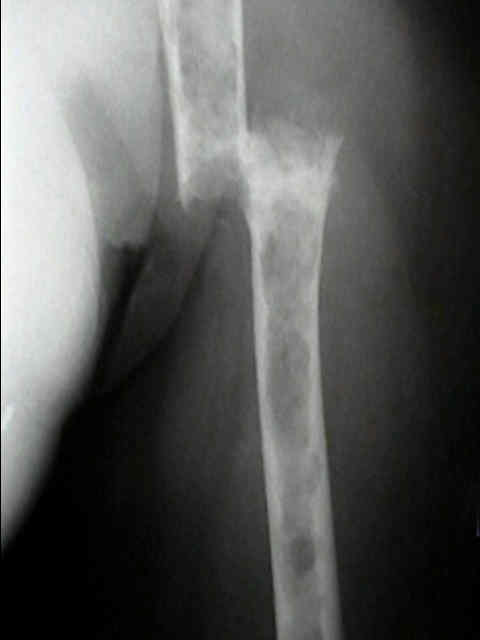

Se localiza, preferentemente, en los huesos donde existe médula ósea roja: vértebras, costillas, esternón, pelvis, cráneo y huesos largos (tercio proximal fémur y húmero).

Las fracturas patológicas de columna o fémur pueden ser el primer

síntoma. Se producen con un traumatismo mínimo o incluso sin trauma.

Radiográficos:

Las radiografías normales pueden mostrar osteopenia difusa.

"Lesiones perforadas" o en "sacabocado" sin ninguna formación de nuevo-hueso circundante. Su diámetro es variable (hasta 5 cm.), redondas y múltiples.

Con el tiempo las lesiones pueden cambiar de osteopenia difusa a más permeativa con patrón destructivo apolillado, y a veces con expansión cortical.

La destrucción del hueso ocurre con poca o ninguna formación de hueso reactivo a menos que haya una fractura patológica.

Los mielomas pueden presentarse como lesión solitaria o más normalmente como un tumor difuso, involucrando múltiples huesos, incluyendo vértebras, cráneo, pelvis y fémures.